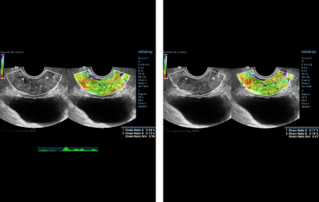

Female pelvic floor anatomy, which developed since the early 20th century, has had a variety of theories, including integral theory, three levels of vaginal support theory, "hammock hypothesis", and three-chamber system. Supporting structures such as pelvic floor muscles, fascia and ligament play an important role in maintaining the normal function of pelvic floor, among which levator ani muscle group is one of the most important supporting structures.